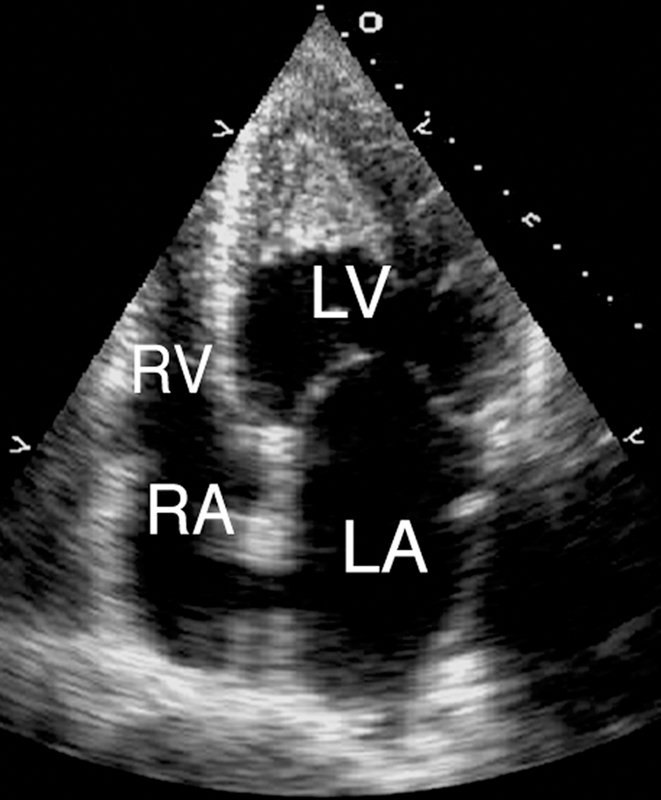

فحوصات تشخيصية لبعض امراض القلب والشرايين التاجية